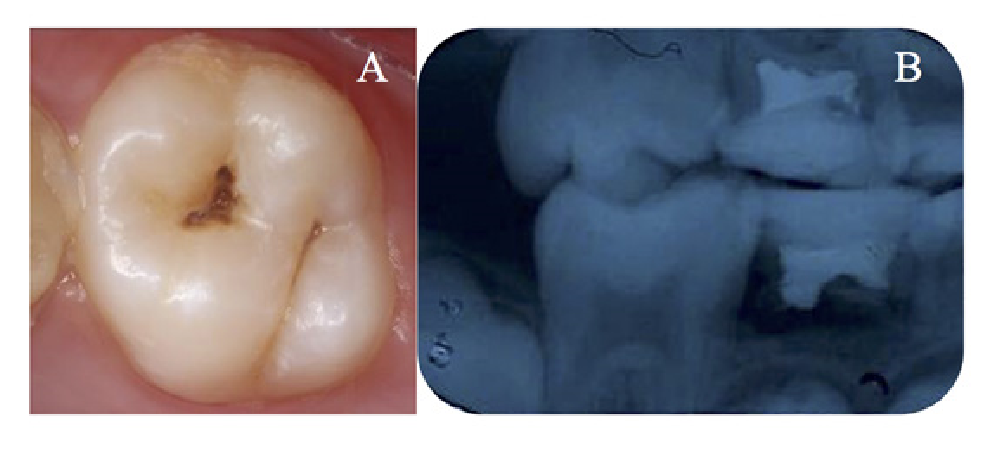

Más específicamente, con respecto a la historia actual de caries, las lesiones activas con puntaje 5 y 3 del ICDAS, fueron diagnosticadas clínicamente en los dientes 16 (Figura 1) y 26 (Figura 2), en el debido orden. Como examen complementario para ayudar en el diagnóstico y con fines de investigación, se realizó un examen radiográfico interproximal (aleta de mordida) y periapical con la ayuda de un posicionador radiográfico infantil, en el que fue posible observar lesiones de caries en la mitad externa de la dentina en ambos dientes, es decir, la lesión del diente 26 también fue un puntaje ICDAS de 5.

Figura 1. Aspecto clínico y radiográfico de la lesión de caries en el diente 16. A) Aspecto clínico del diente 16 mostrando una lesión de caries activa puntuación ICDAS 5. B) Radiografía interproximal que muestra una imagen radiolúcida que sugiere una lesión de caries en la mitad externa de la dentina del diente 16.